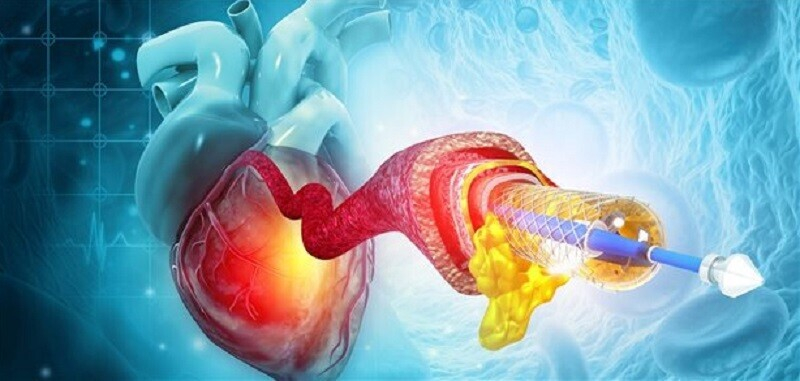

- интервенционной, предусматривающей введение трубки-катетера, через которую в сосуды сердца поступает контрастное вещество;

- Далее выполняют прокол кровеносного сосуда для введения катетера, который хирург постепенно продвигает к устью артерии. После достижения нужного участка в катетер подается контрастное вещество, достигающее сосудов сердечной мышцы.

- В это время оборудование выполняет рентген-съемку и видеозапись процесса наполнения кровеносных сосудов контрастным веществом.